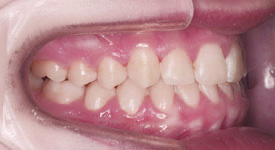

Crowding Upper